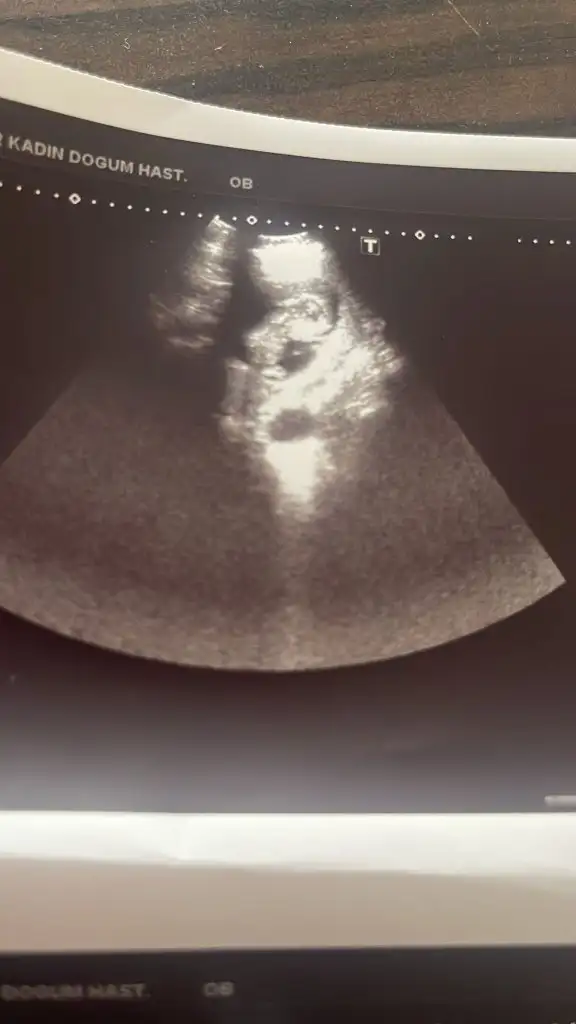

Banada tahminde bulunurmusunuz rica etsem 🙏🏻☺️

Bana da tahminde bulunur musunuz 13 haftalık olduk doktor erkeğe benziyor ama 16 haftalıkken belli olur dedi❤️